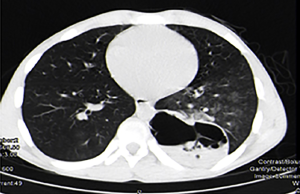

Pulmonary aspergillosis can manifest as invasive aspergillosis, allergic bronchopulmonary aspergillosis (ABPA) or cavitary pulmonary aspergillosis (Figures 4,5). In tuberculosis endemic countries of the world, the healed tubercular cavities act as the much needed nidus for saprophytic colonization of Aspergillus fumigatus. The fungal toxins erode the tissues and can cause haemoptysis when a vessel wall is eroded. Presence of the characteristic fungal ball with ‘air crescent’ in chest X-ray or CT scan clinches the diagnosis. Surgery in the form of pulmonary resection is the mainstay of treatment although intraoperative period can be complicated by dense intra-pleural adhesions, hemorrhage, air leak, disruption of cavity and seeding of the fungus with high morbidity (13-15). Surgical mortality ranges from 0% to 22.6% and reported recurrence rate is 5% (16).

These images demonstrate that the degree of complexity of pulmonary pathology is very challenging in the developing world. Late presentation to the clinician and non compliance to treatment regime are the main causes of such complex case scenarios. Due to late presentation the disease distorts the pulmonary anatomy and physiology. Lung collapse, atelectasis, adhesions, loculated effusions, thick cortex for decortications are frequently encountered. The amount of perioperative blood loss and risk of septicemia are very high.